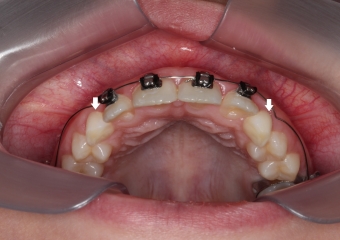

Cirurgia com fio de aço instalado para tracionamento dos caninos permanentes

Dentes em tracionamento